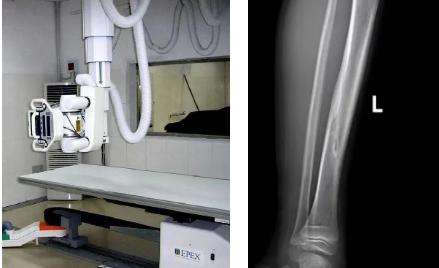

1.定期復查。一般于骨折后2-4周,骨折進入骨痂期,骨折斷端有新生骨形成,呈明顯高密度,無論是X線或是CT,都能比較清晰觀察到,通過前后圖像對比,較容易診斷隱匿性骨折。

2.CT或MRI檢查。CT是斷面成像,不會出現重疊而導致漏診,同時CT還可以進行多平面的重建,除了發現X線無法發現的骨折外,還可以三維直觀的顯示骨折的程度,對臨床治療有指導意義。CT無法發現骨裂、不全骨折或者骨挫傷,對軟組織的損傷診斷也有局限性,MRI就可以發現這些損傷。